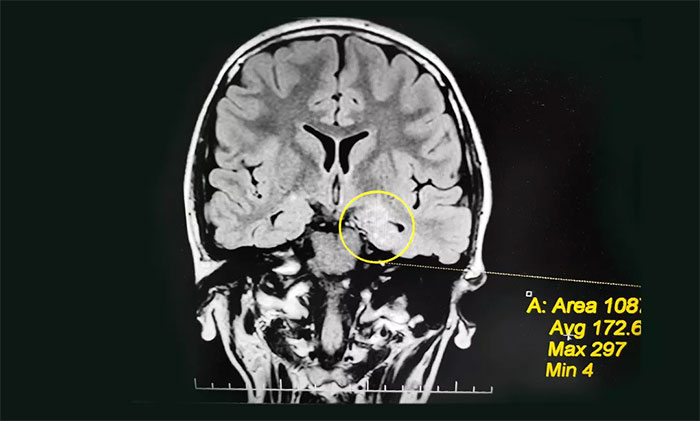

入院后,佳欣接受了一系列检查:行24小时长程脑电图监测,提示异常脑电图;MRI检查,左侧颞叶海马区影像改变,左侧海马神经元受损、局部代谢旺盛,考虑左侧海马区轴内变性病变,考虑致癫灶可能。

为佳欣诊治的杨忠旭教授查看了各项检查报告,详细了解相关病情后,考虑佳欣因难产导致大脑缺血、缺氧,而海马对这种情况的耐受较差,极易造成其内的神经细胞受损,时间长了就会发展成海马硬化。成年后,近一半以上的病人会因此患上顽固性癫痫。

杨忠旭教授指出,佳欣的癫痫诊断明确,经系统药物治疗无任何改善,确诊为难治性癫痫,应用现代神经影像学技术和电生理监测技术,能明确引起癫痫发作的“责任病变”,且手术指征明显,未见明显手术禁忌症。

▲ 通过系列检查评估,最终明确患者致癫灶